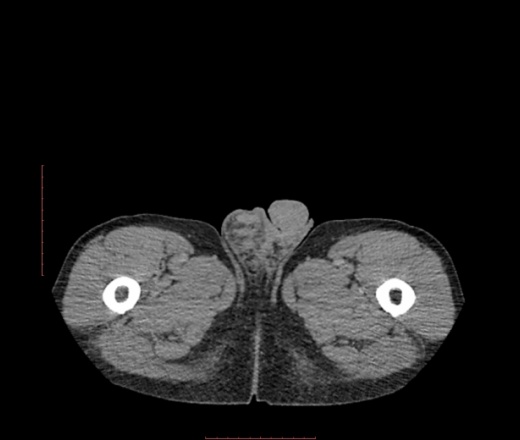

В печени похоже на гемангиому, в малом тазу вижу изменения в паховом канале, в правом яичке.

Спасибо за совет. Добавил изображнеия. В почках кисты*. А какова связь образоваия с правой паховой областью?

Липосаркома, а вниз распространяется по околопочечным пространствам.

липосаркома разной степени дифференцииации